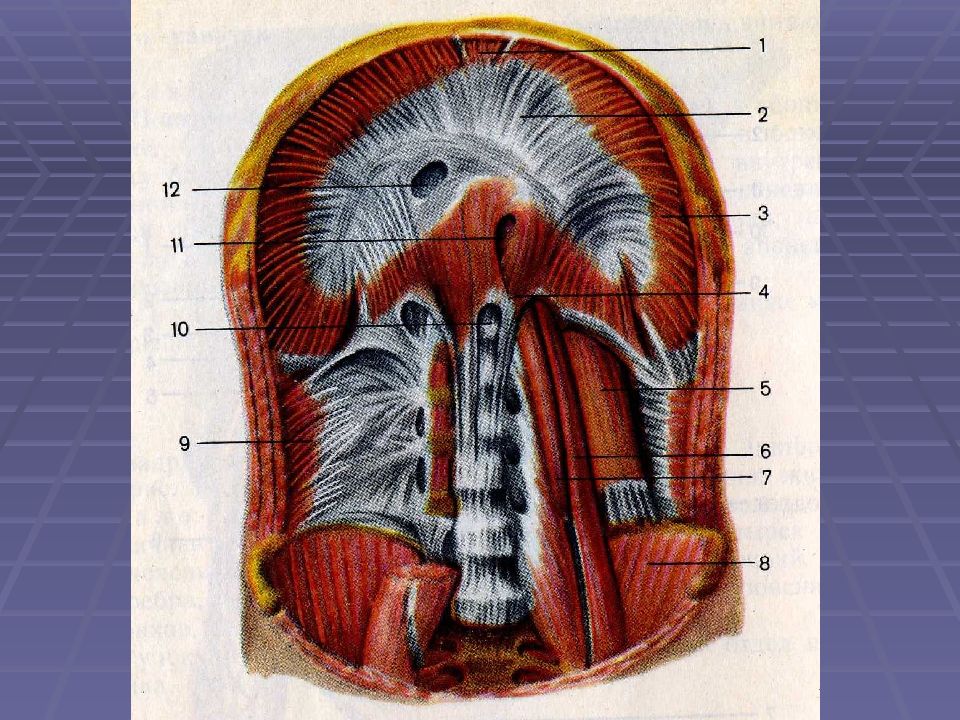

Анатомия диафрагмы и треугольника Бохдалека

Раздел: Визуальный дайджест